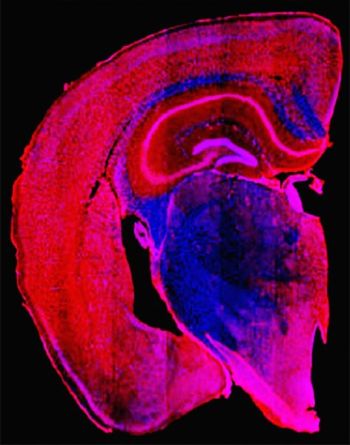

Degli scienziati hanno usato un composto per prevenire e invertire i danni cerebrali causati dalla tau nei topi. (Fonte: Miller lab, Washington University, St. Louis, MO)In uno studio su topi e scimmie, dei ricercatori hanno dimostrato di poter prevenire e invertire alcuni dei danni cerebrali causati dalla forma tossica della proteina tau.

Le iniezioni del composto negli spazi pieni di liquido del cervello dei topi hanno impedito la formazione di grumi di tau nei topi di 6-9 mesi di età e sembrano averne invertito il raggruppamento nei topi anziani. Il composto ha anche permesso ai topi anziani di vivere più a lungo e di avere un cervello più sano rispetto ai topi che hanno ricevuto un placebo. Inoltre, il composto ha impedito ai topi anziani di perdere la capacità di costruire nidi.